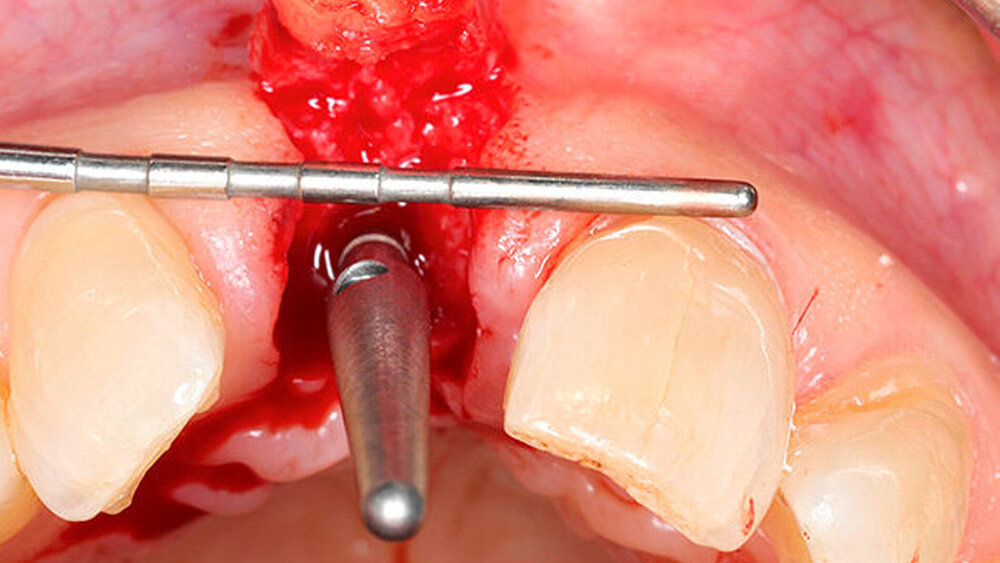

In welchen klinischen Anwendungen bietet das Implantat Vorteile?Hermann:Das neue CAMLOG PROGRESSIVE-LINE Implantat besticht durch sein innovatives parallel-konisches Makrodesign mit einem speziellen Gewinde, bei gleichzeitig bewährter Prothetikschnittstelle der Camlog-Linie. Dies bedeutet, dass in der chirurgischen Phase mit diesem Implantat eine zuverlässige Primärstabilität erzielt werden kann, speziell bei schwierigen anatomischen Voraussetzungen, wie z. B. bei der Sofortimplantation, bei reduzierter Kieferkammbreite oder konkav verlaufenden Alveoloarkämmen sowie bei weichem Knochen im Oberkiefer. Aufgrund des krestalen Verankerungsgewindes sehen wir zudem einen Vorteil bei der Platzierung des Implantats im Zusammenhang mit einer simultanen, offenen Sinusbodenelevation bei stark reduzierter Restknochenhöhe (2–3 mm). Auch einzeitige Verfahren lassen sich einfacher durchführen. Denn auch im kompromittierten Knochen erreicht das Implantat eine hohe vorhersagbare Primärstabilität.

Sind dann auch eher Sofortversorgungsprotkolle umzusetzen?Hermann:Die erzielte Primärstabilität ist in den meisten Fällen so hoch, dass eine sofortige provisorische Versorgung/Belastung möglich ist. Somit können wir unseren Patienten effiziente Behandlungsabläufe anbieten. Die Effizienz zeigt sich beispielsweise auch bei der Reduktion der Bohrschritte durch ein flexibles Bohrprotokoll. Gerade im weichen Knochen benötigen wir meist nur drei Bohrschritte bis zur Insertion des Implantats und erzielten eine exzellente Primärstabilität durch eine geringere Aufbereitung des Implantatbetts. Auf den zusätzlichen Einsatz nicht-ablativer Techniken (Osteotome) kann häufig verzichtet werden. Ein Teil der 80 von uns gesetzten PROGRES ‧ SIVE- ‧ LINE Implantate befindet sich bereits in der prothetischen Nachkontrolle. Das klinische und prothetische Outcome ist hervorragend. Es gibt weder chirurgische Komplikationen noch Probleme bei der Einheilung, und die prothetische Versorgung funktioniert perfekt.